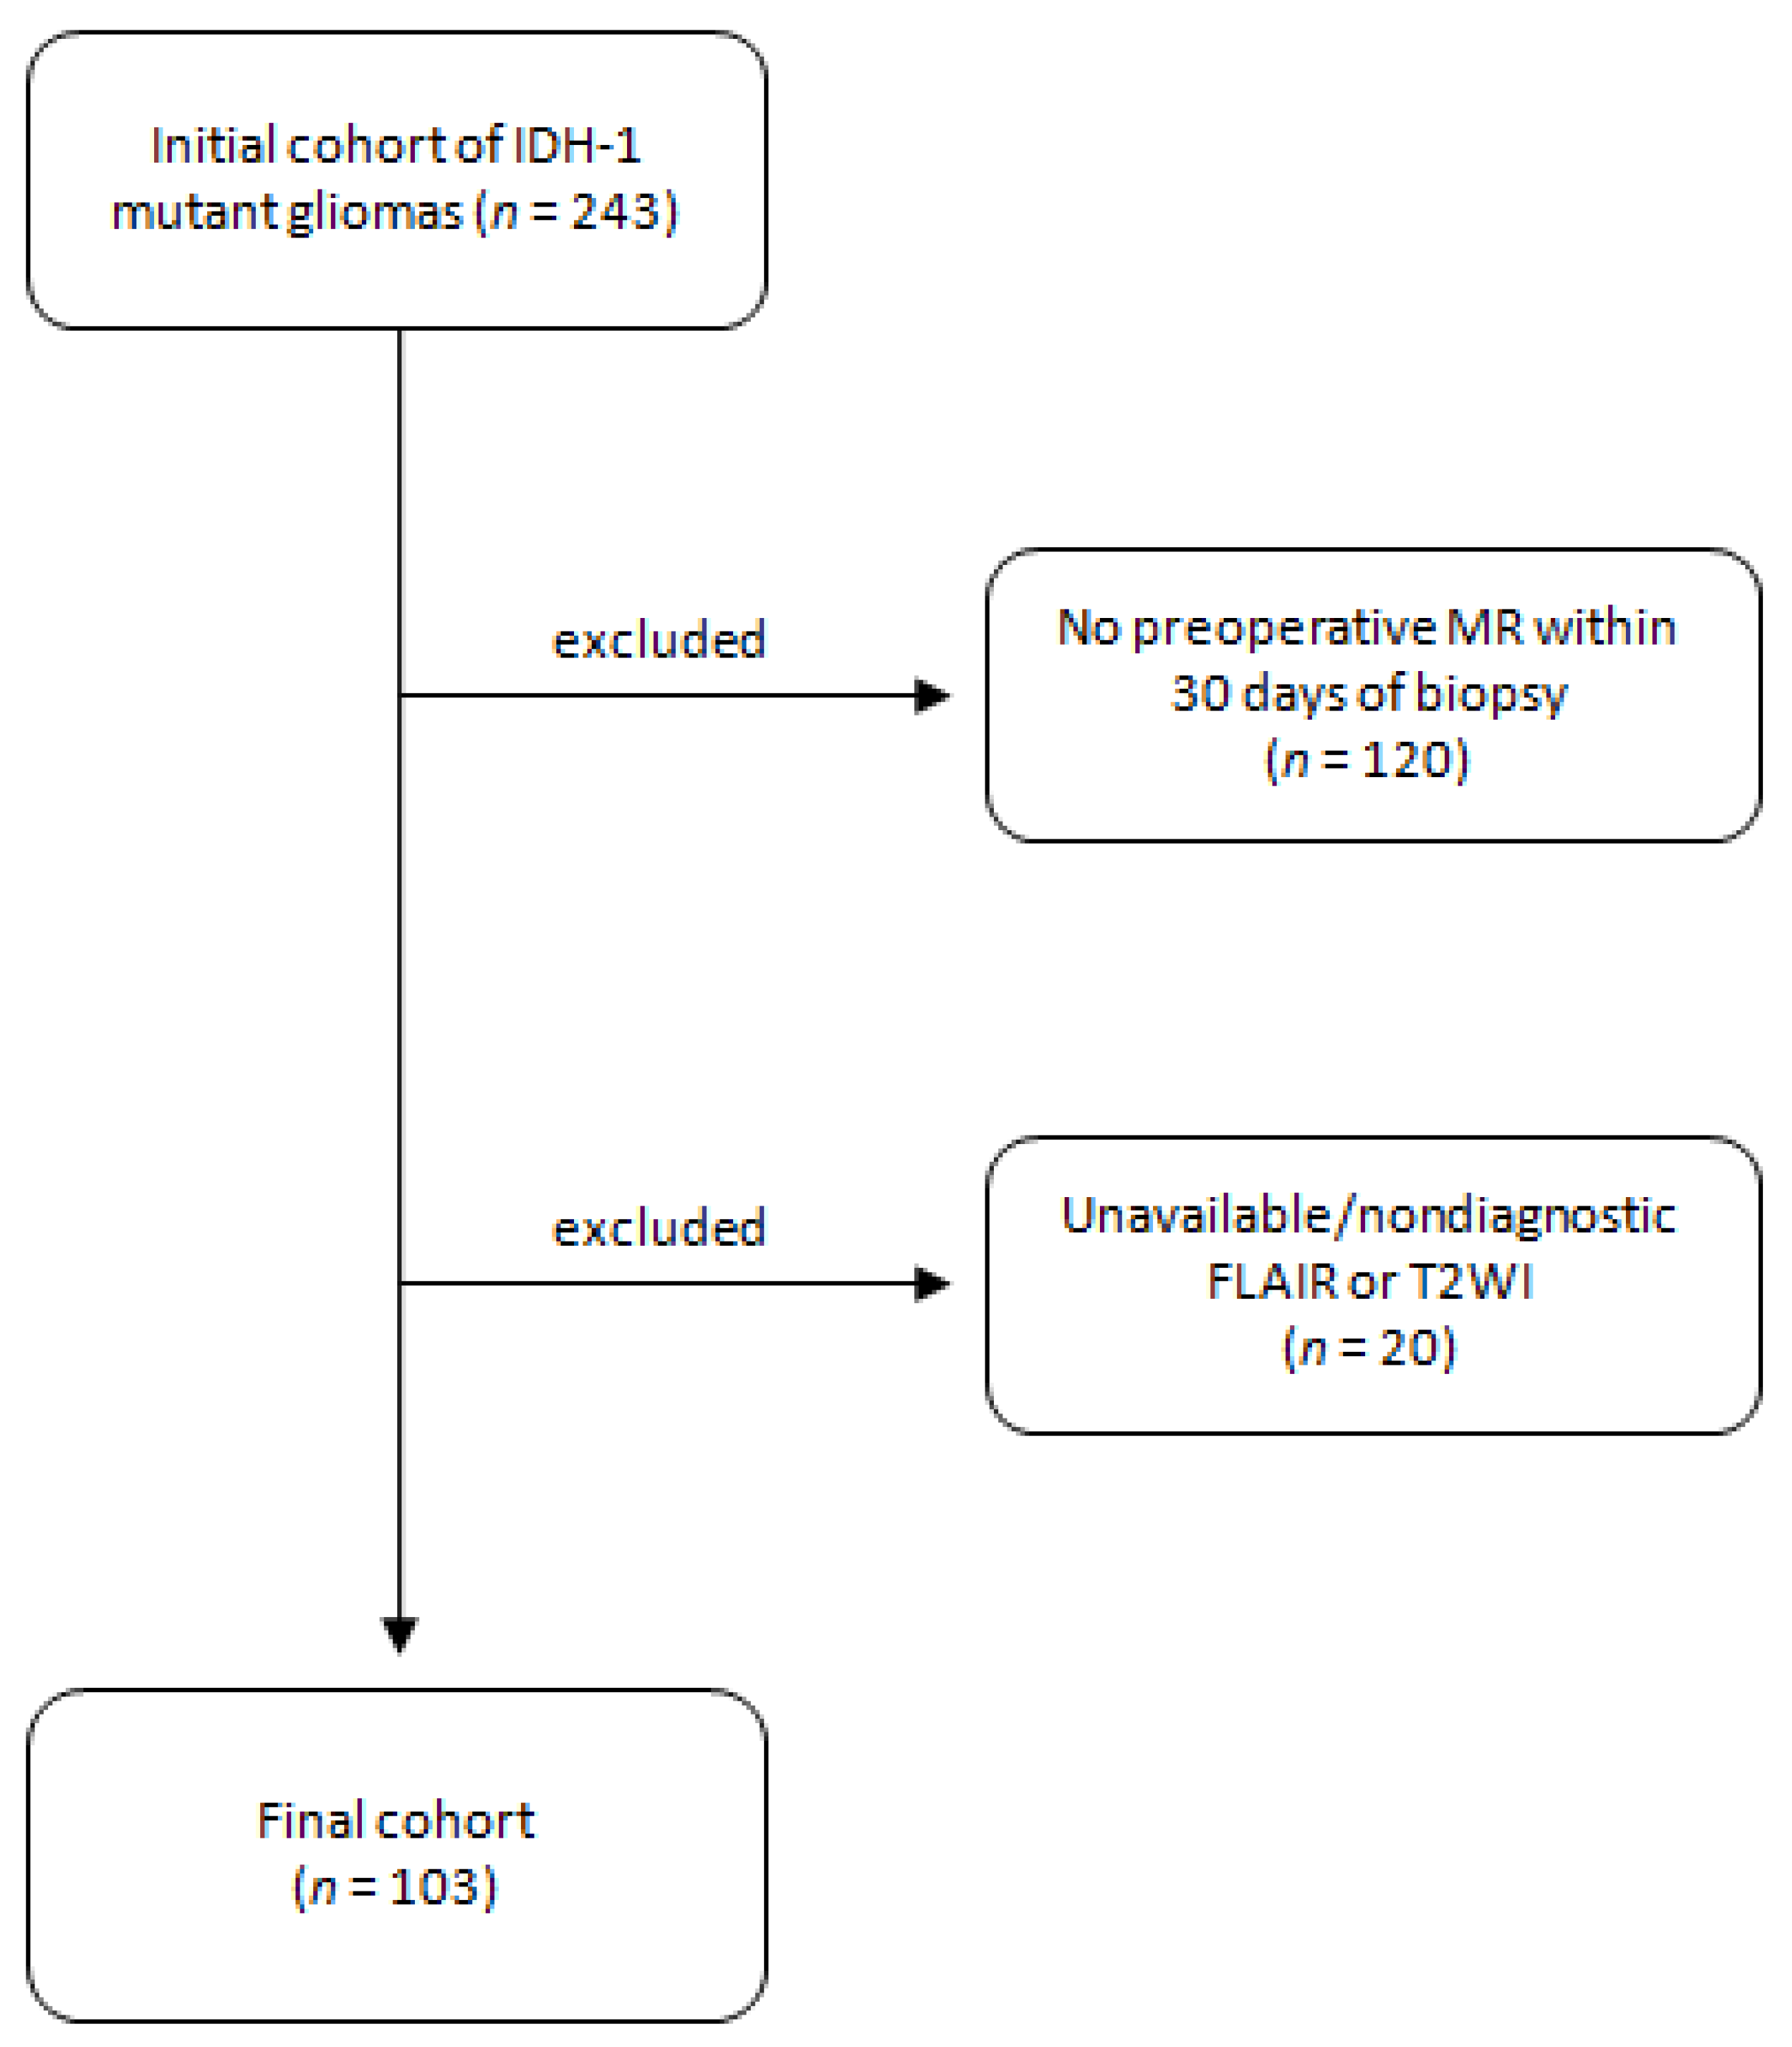

2.1. Patient Selection